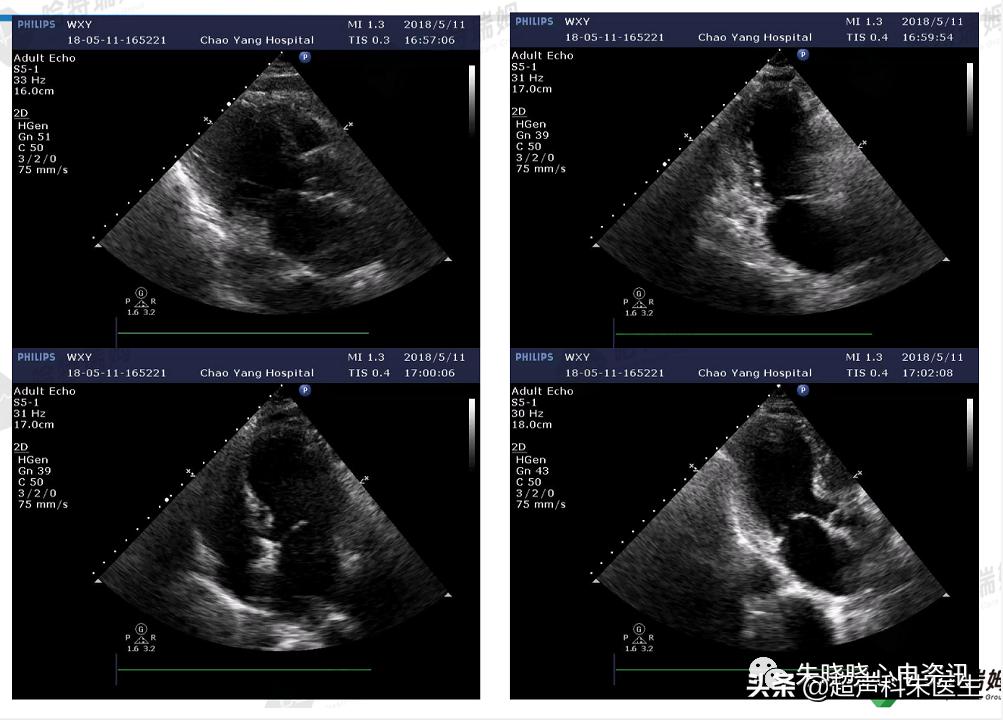

病例2:应激性心肌病

患者女性,69岁,主因“发作胸痛、胸闷1年,再发加重8小时”入院。既往史:1年前不稳定性心绞痛,CAG示双支病变,一直予药物治疗,高血压病史20年,1年半前*房行**颤射频消融术,入院前1天其子跑步后猝死。经心脏彩超及左室造影后,证实为应激性心肌病。

图17:广泛导联T波倒置伴QT间期延长

图18:入院后心脏彩超

Takotsubo心肌病又称心尖球形综合征,表现为一过性心尖或心脏中段收缩功能障碍,但缺乏冠脉狭窄证据。其机制尚不清楚,可能与儿茶酚胺引起的心肌顿抑等因素有关。

应激性心肌病的特征性心电图表现:广泛导联的ST段抬高,但缺乏对应导联的ST段压低,多出现在胸前导联,ST段抬高在前,进而出现T波倒置,QT间期延长,较急性冠脉综合征更为明显,可持续数天至数周。